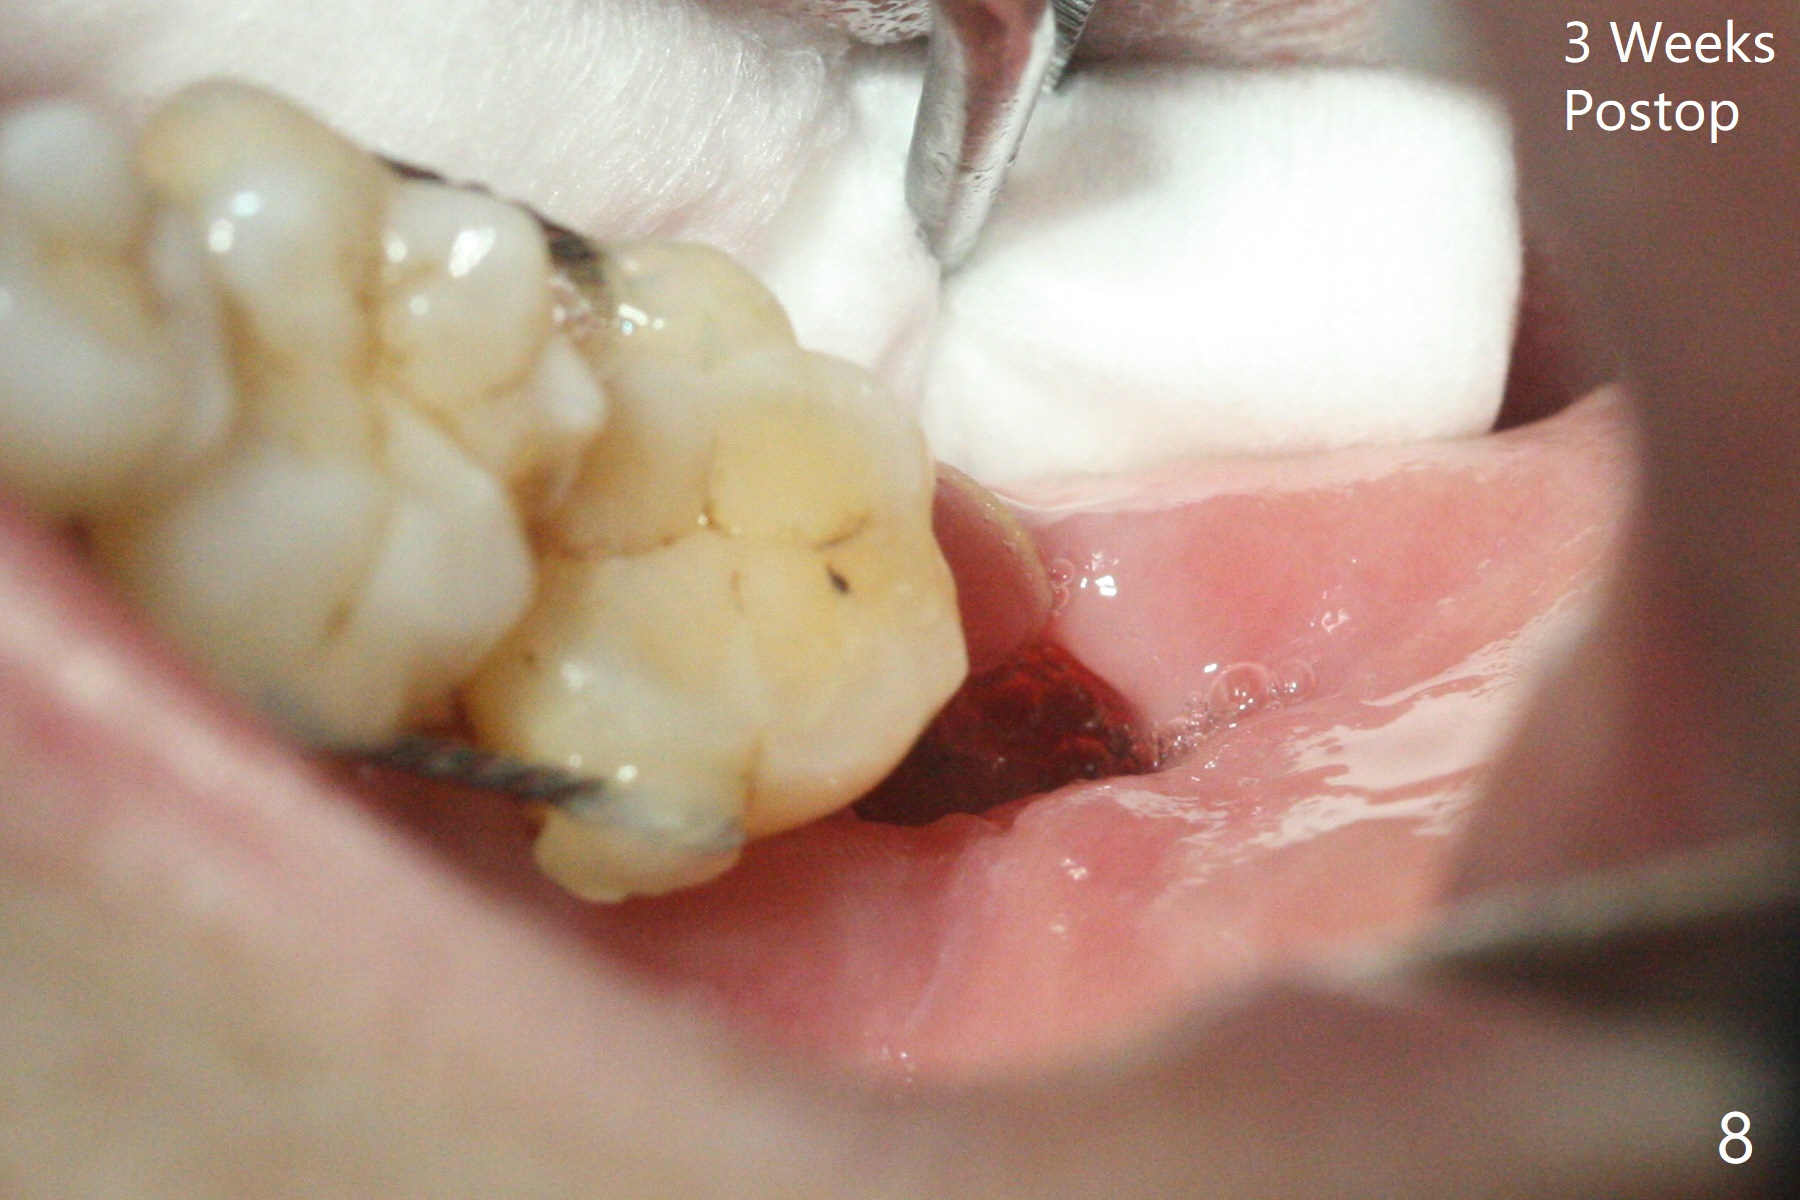

65岁女,南方人(广州),主诉左下肿胀,8舌侧粘膜穿孔(图一(舌侧观):<),初步问诊,回答:“全身没问题”,详细问诊:骨质疏松,静脉注射Reclast两年,准备拔除使用PRF修复缺损,全景片显示7远中骨质吸收严重(图二),因此8拔出后,牙槽窝塞入胶原塞(图五:C),将粘性骨粉放置7近中,远中(图五:白*)以及颊侧(黑*),把一片PRF膜覆盖骨粉(7颊侧,8牙槽窝口),另外一片放置于8舌侧穿孔(图四:箭头)颊侧,促进愈合,然后使用4-0 PGA缝合(图三(颊侧观),图四(舌侧观))。术后5天用钢丝(图六:*)和树脂固定松动牙,并且降低咬合。舌侧穿孔正在愈合(图七:>)。虽然术后三周智齿伤口裂开,但是没有症状,病人满意第二磨牙不再松动(图八),开始深洗。下次复诊拍摄根尖片观察骨质愈合。术后二个月第二磨牙远中没有骨质再生(图九),临床上远中牙根暴露。